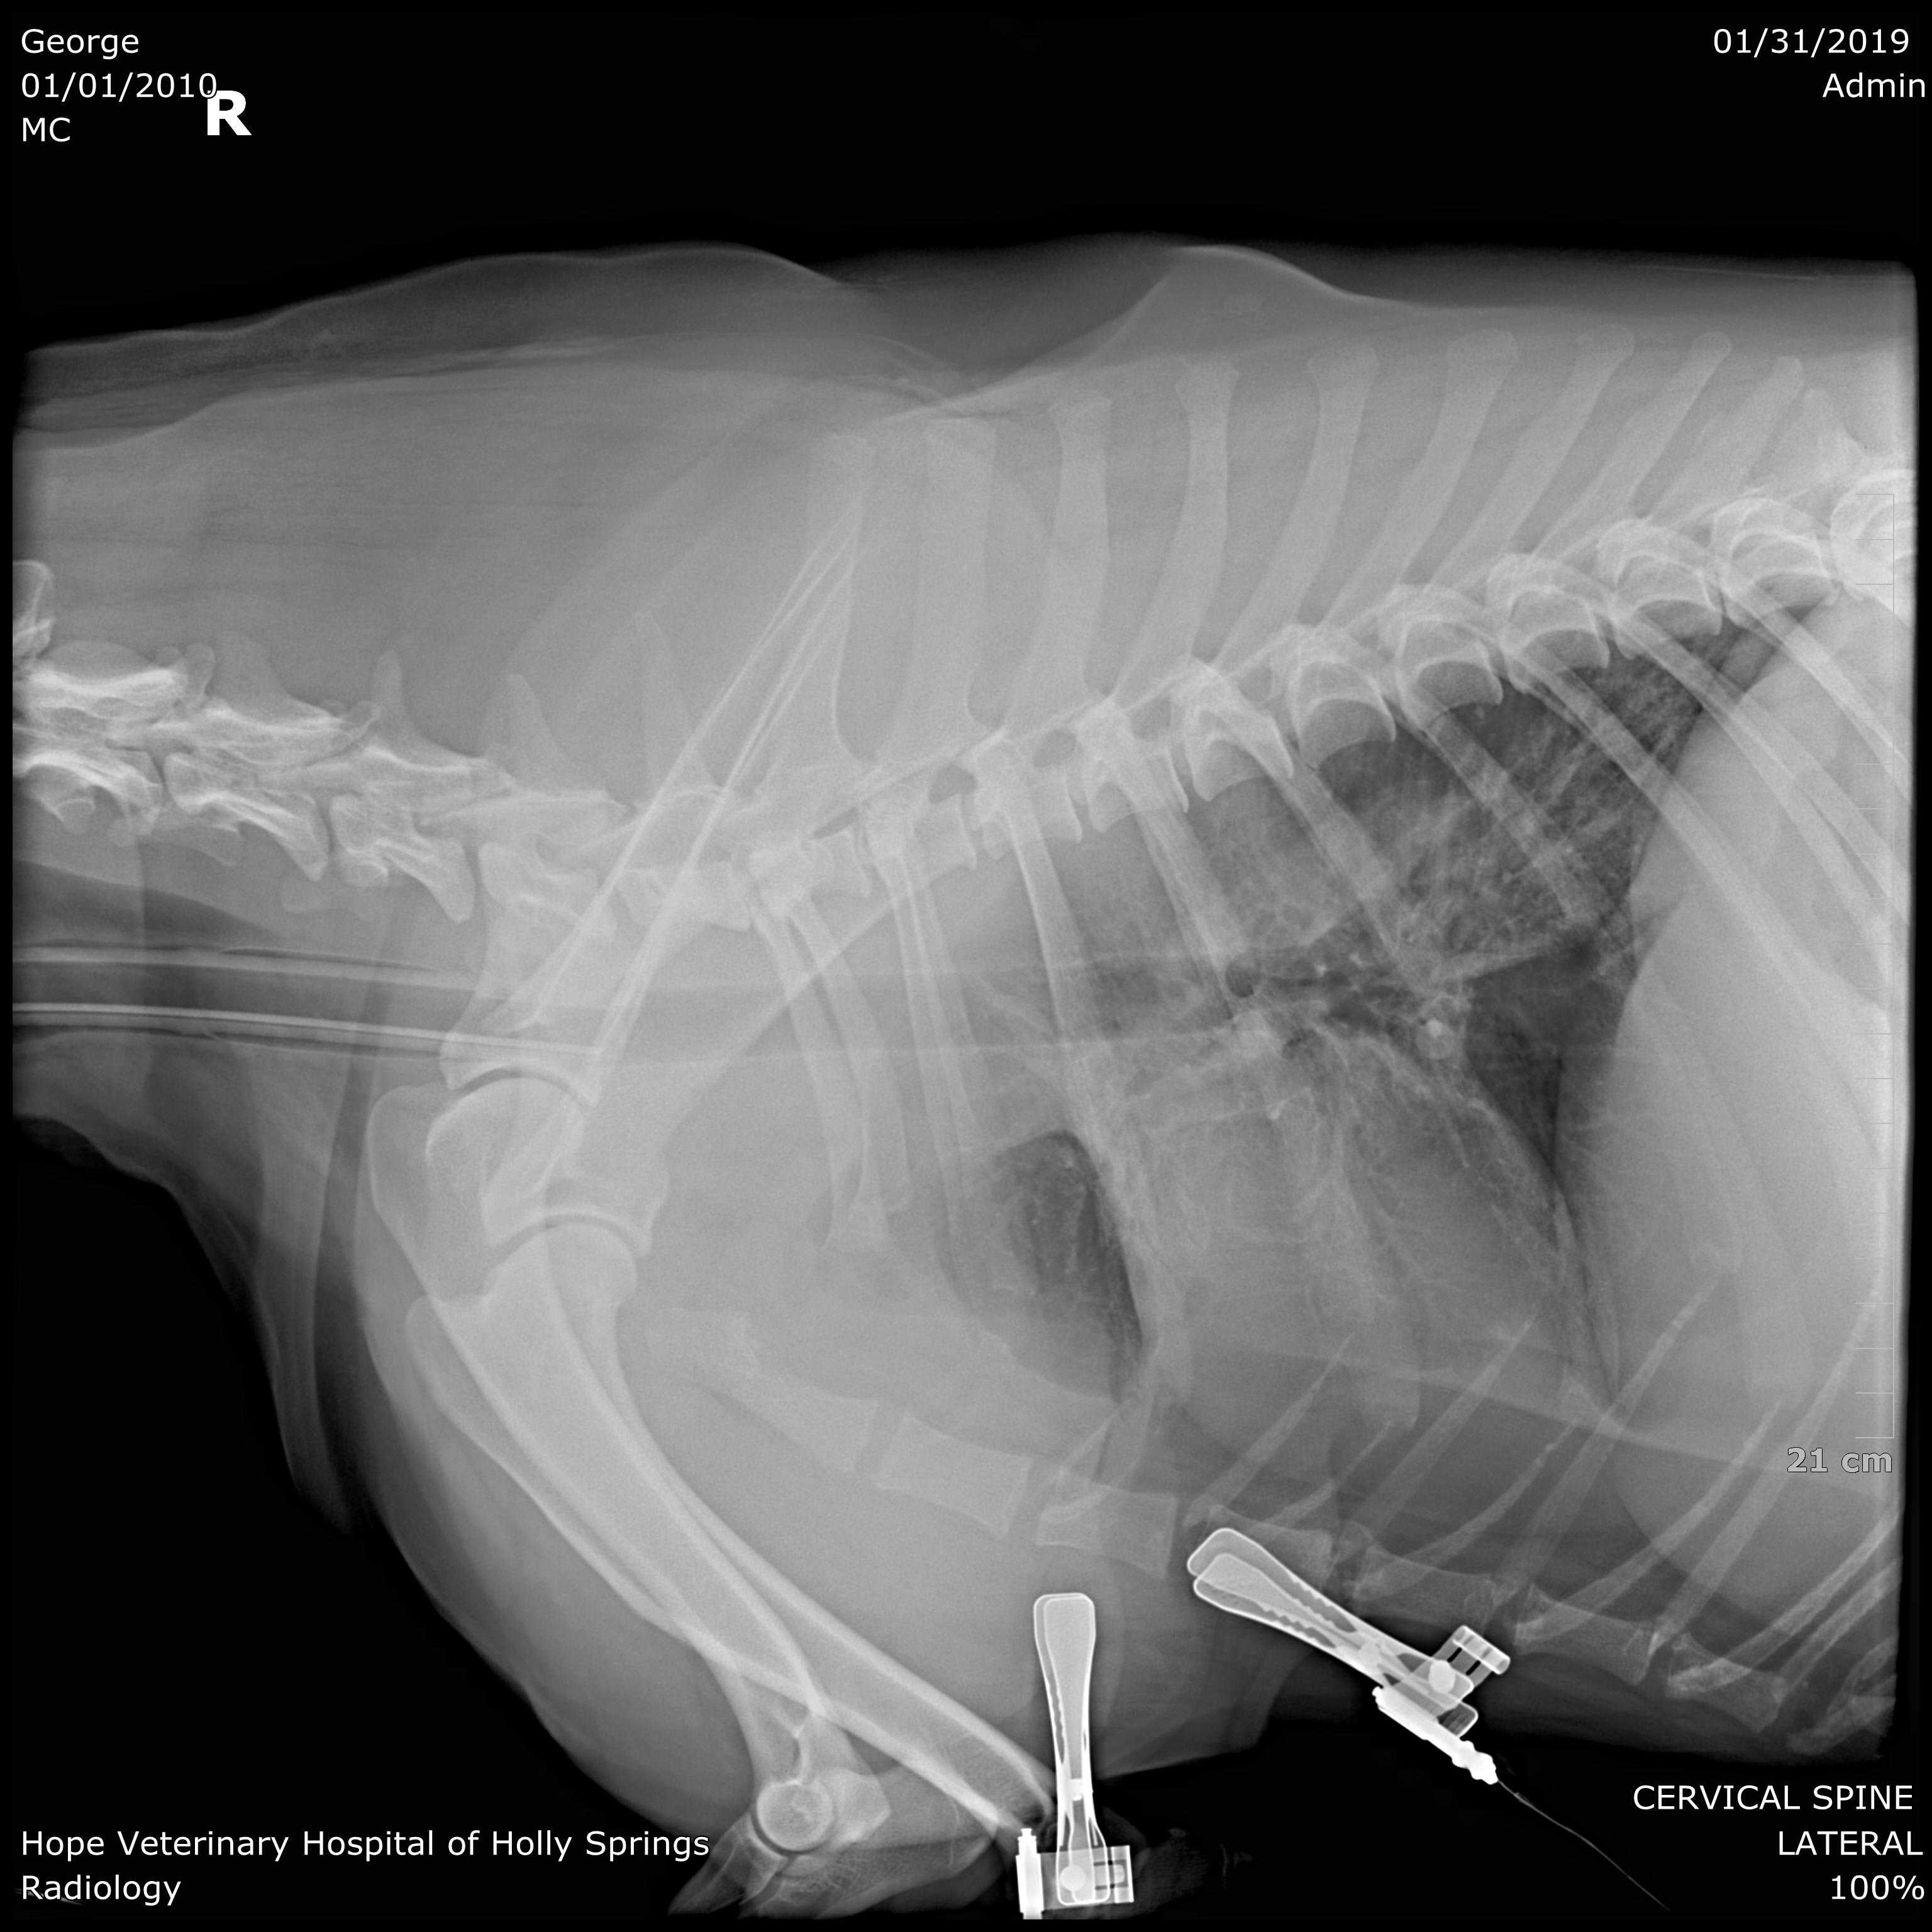

Pet's info: Dog | Mixed Breed Large (61lb +) | Male | neutered | 8 years and 9 months old | 83 lbs

We are looking for a second opinion. Do you see anything remarkable in these xrays?

Hello and welcome to Petco Pet Education Center, formerly Petcoach. Looking at x-rays that are not viewed with a proper screen can be very difficult, so it can be easy to miss things on these images. I can see the following: 1. The heart does NOT appear to be enlarged 2. The lungs have a slight increased opacity around the peri-hilar region (this can sometimes be associated with heart disease) 3. There is poor detail in the abdomen (this could be due to 'chest settings' and not actually 'real') 4. There is some discospondylosis present in the lumbar vertebrae (bridging between two vertebrae- likely inconsequential) 5. There is no sign of free fluid or free gas in the chest cavity 6. On the second image there is some gas in the esophagus, but this might be artifact of being sedated. 7. On the second image the lungs seem more 'white' then they should be, in the caudo-dorsal region. I recommend that if you are still unsure, have the x-rays sent to a radiologist specialist, as they will get a format they can better manipulate and give you better information about the lung parenchyma (tissue itself of the lungs) which is very hard to evaluate with the images you have provided. I don't see anything too remarkable in these x-rays. If you tell us what is clinically wrong with George we can look at the images again with his clinical picture in mind. Best of luck with George!